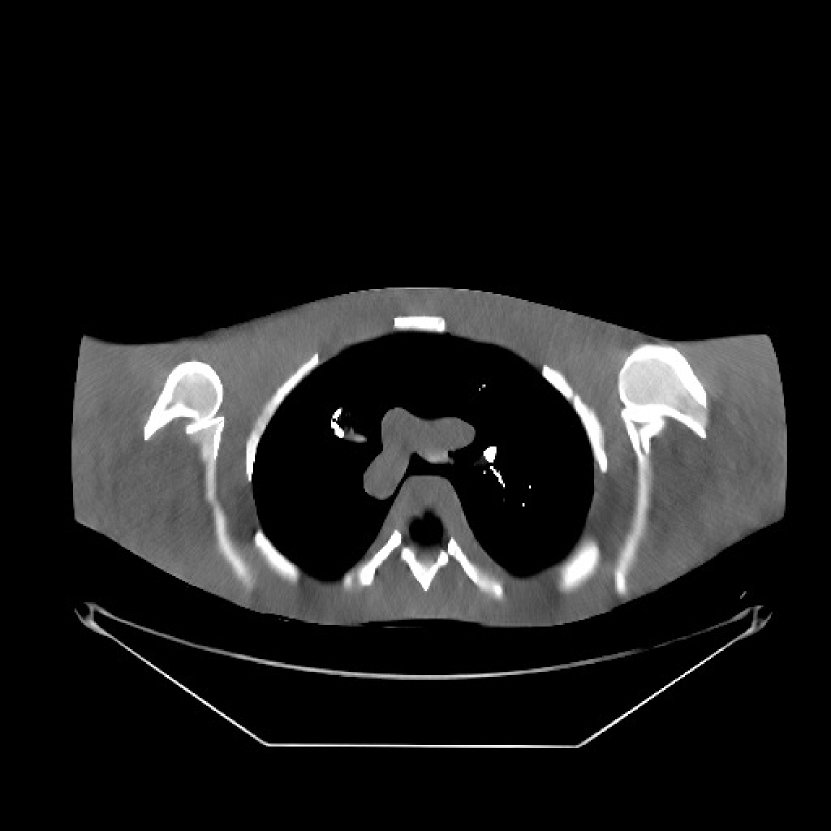

We used the pre-learned union of 15 square transforms from the XCAT phantom simulations to reconstruct the synthesized helical chest scan volume of size 420×420×222420420222{420\times 420\times 222} with Δx=Δy=1.1667subscriptΔ𝑥subscriptΔ𝑦1.1667\Delta_{x}=\Delta_{y}=1.1667 mm and Δz=0.625subscriptΔ𝑧0.625{\Delta_{z}=0.625} mm. The sinograms were of size 888×64×3611888643611888\times 64\times 3611. Since the clinical data is synthesized via the PWLS-ULTRA reconstruction, the noise model for this synthesized data is obscure, making it difficult to determine appropriate low-dose levels for such data. We tested the radiation dose of I0=1×104subscript𝐼01superscript104I_{0}=1\times 10^{4} with an electronic noise variance the same as the XCAT phantom simulation, i.e., σ2=25superscript𝜎225\sigma^{2}=25. The percentage of non-positive pre-log measurements for the synthesized clinical data in this case was around 0.14%percent0.140.14\%. Such non-positive values were replaced by 1×1051superscript1051\times 10^{-5} for PWLS-based methods. Fig. 8(a) shows the “true” clinical image that was reconstructed from real clinical regular-dose sinogram using the PWLS-ULTRA method.

Refer to caption

(a)

(b)

Figure 8: (a) “true” clinical image (HU), (b) the reconstruction (HU) of the synthesized data with PWLS-EP for I0=1×104subscript𝐼01superscript104I_{0}=1\times 10^{4} with βep=215subscript𝛽𝑒𝑝superscript215\beta_{ep}=2^{15}. The central axial, sagittal, and coronal slices of the volume are shown.

Similar to the XCAT phantom simulation, the initial image for both SPULTRA and PWLS-ULTRA was a reconstruction obtained using PWLS-EP. We set the regularizer parameter βepsubscript𝛽𝑒𝑝\beta_{ep} for PWLS-EP to 215superscript2152^{15} to generate a smoother (with less noise) initial image, which led to good visual image equality for the SPULTRA and PWLS-ULTRA reconstructions. Since the optimization problem for PWLS-EP is strictly convex, we simply initialized PWLS-EP with a zero image. Fig. 8(b) shows the PWLS-EP reconstructed image for I0=1×104subscript𝐼01superscript104I_{0}=1\times 10^{4}. We set the regularizer parameters for both PWLS-ULTRA and SPULTRA as γc=5×104subscript𝛾𝑐5superscript104\gamma_{c}=5\times 10^{-4}, and β=1.5×104𝛽1.5superscript104\beta=1.5\times 10^{4}.